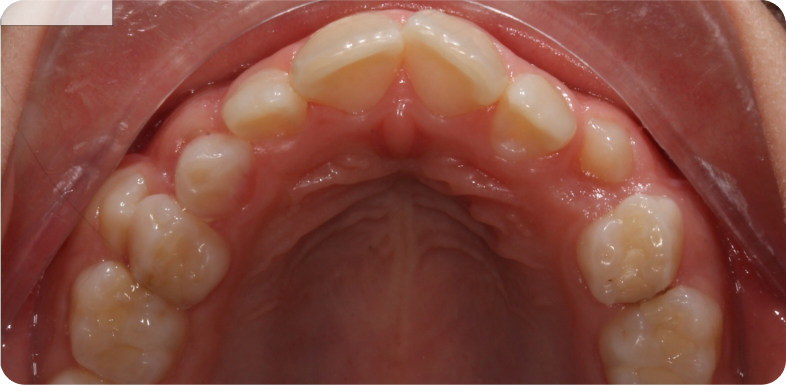

- une gouttière de contention maxillaire / plaque palatine un mois après la dépose, à porter la nuit, pendant plusieurs mois après la fin du traitement.

Cas cliniques